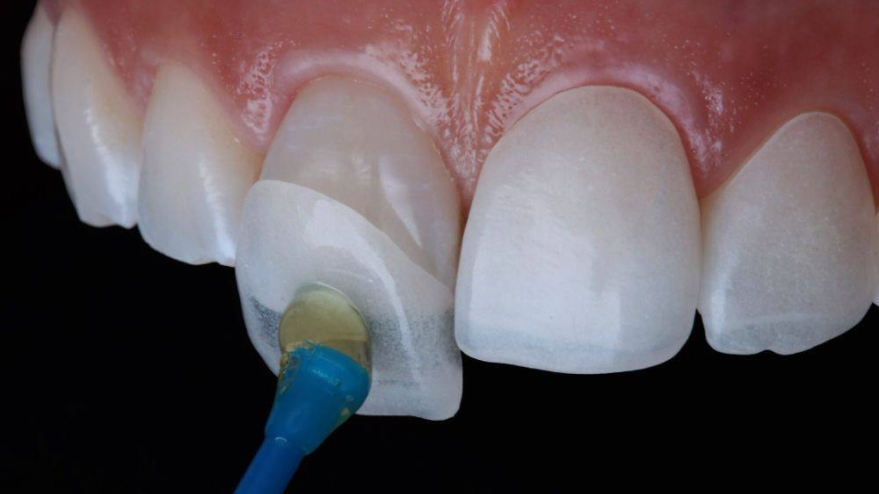

3. Подготовка зубов

под микроскопом обтачиваем зуб для надежной фиксации

Керамические виниры изготавливаются по полному цифровому протоколу. Это исключает любые неточности и врачебные ошибки.